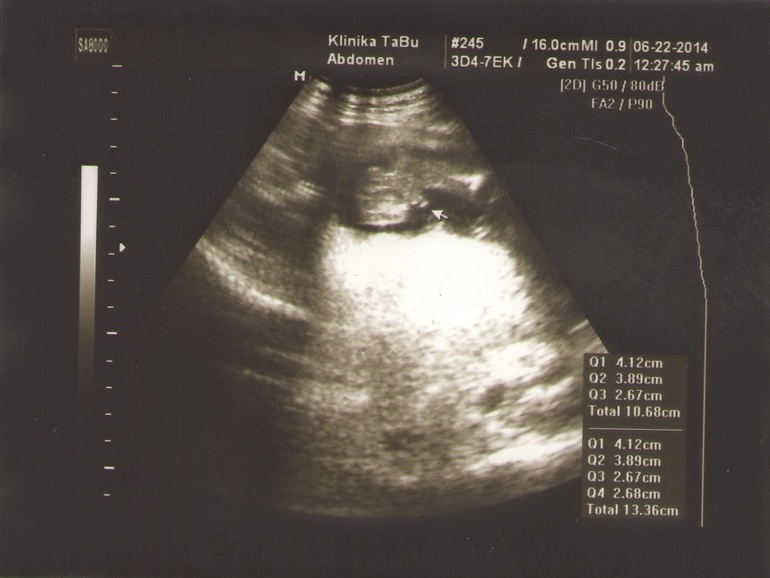

УЗИ, КТГ, доплерНам на узи делали три фото, с двумя разобрались, а вот с одним...ну никак не можем понять ничего, странное фото! Я вообще не ориентируюсь, где тут у моего ребенка что! Можете кто нибудь расшифровать и показать мне где что!!! Кому не трудно! Где профиль ребенка...голова вроде понятно что справа и то не факт.......смотрим смотрим с мужем а понять не можем, и так и сяк крутили!

то что ближе к левой части, большое белое — это головка, смотрит на вас, если присмотреться, то есть 2 черных шарика, один выше, другой под ним, это глазки, левее получается виден серый лоб, а правее все белое — это челюсти и подбородок. белая полоса сверху поду углом — это ручка. а большой шар справа и выше — это животик, черный шарик снизу в нем — это желудок. и рядом с желудком еще белая полоса горизонтально в верх — это ребра, а ниже белая палочка небольшая — это вторая ручка

фотография действительно не самая удачная, но продолжайте вглядываться! и вы найдете на лице глазки, особенно правый, его лучше видно, рядом с рукой ( сверху), рука к виску направлена, а вот левый (нижний) сложнее, он не ровно под верхним (правым), а чуть правее, так как головка под наклоном:))) а над глазиком даже надбровная дуга видна (у нижнего глаза левее темного пятна видна белая полоса) пытайтесь, вглядывайтесь:) и дорисовывайте в мыслях:)

Мне кажется,что лежит спинкой кверху. Справа голова,вниз-носик и сосет кулачек)))А на правую ручку опирается. Ножек почти не видно-очень расплывчато...

Мне тоже кажется, что слева ножки, внизу одна ручка, вверху вторая, посередине туловище, а голова повернута лицом к нам и вон глазки видно. А вообще, фотки конечно жесть))) Аппарат у них что ли старый там?

Мне тоже виднеется лицо пря по центру! Но что тогда справа круглое...))